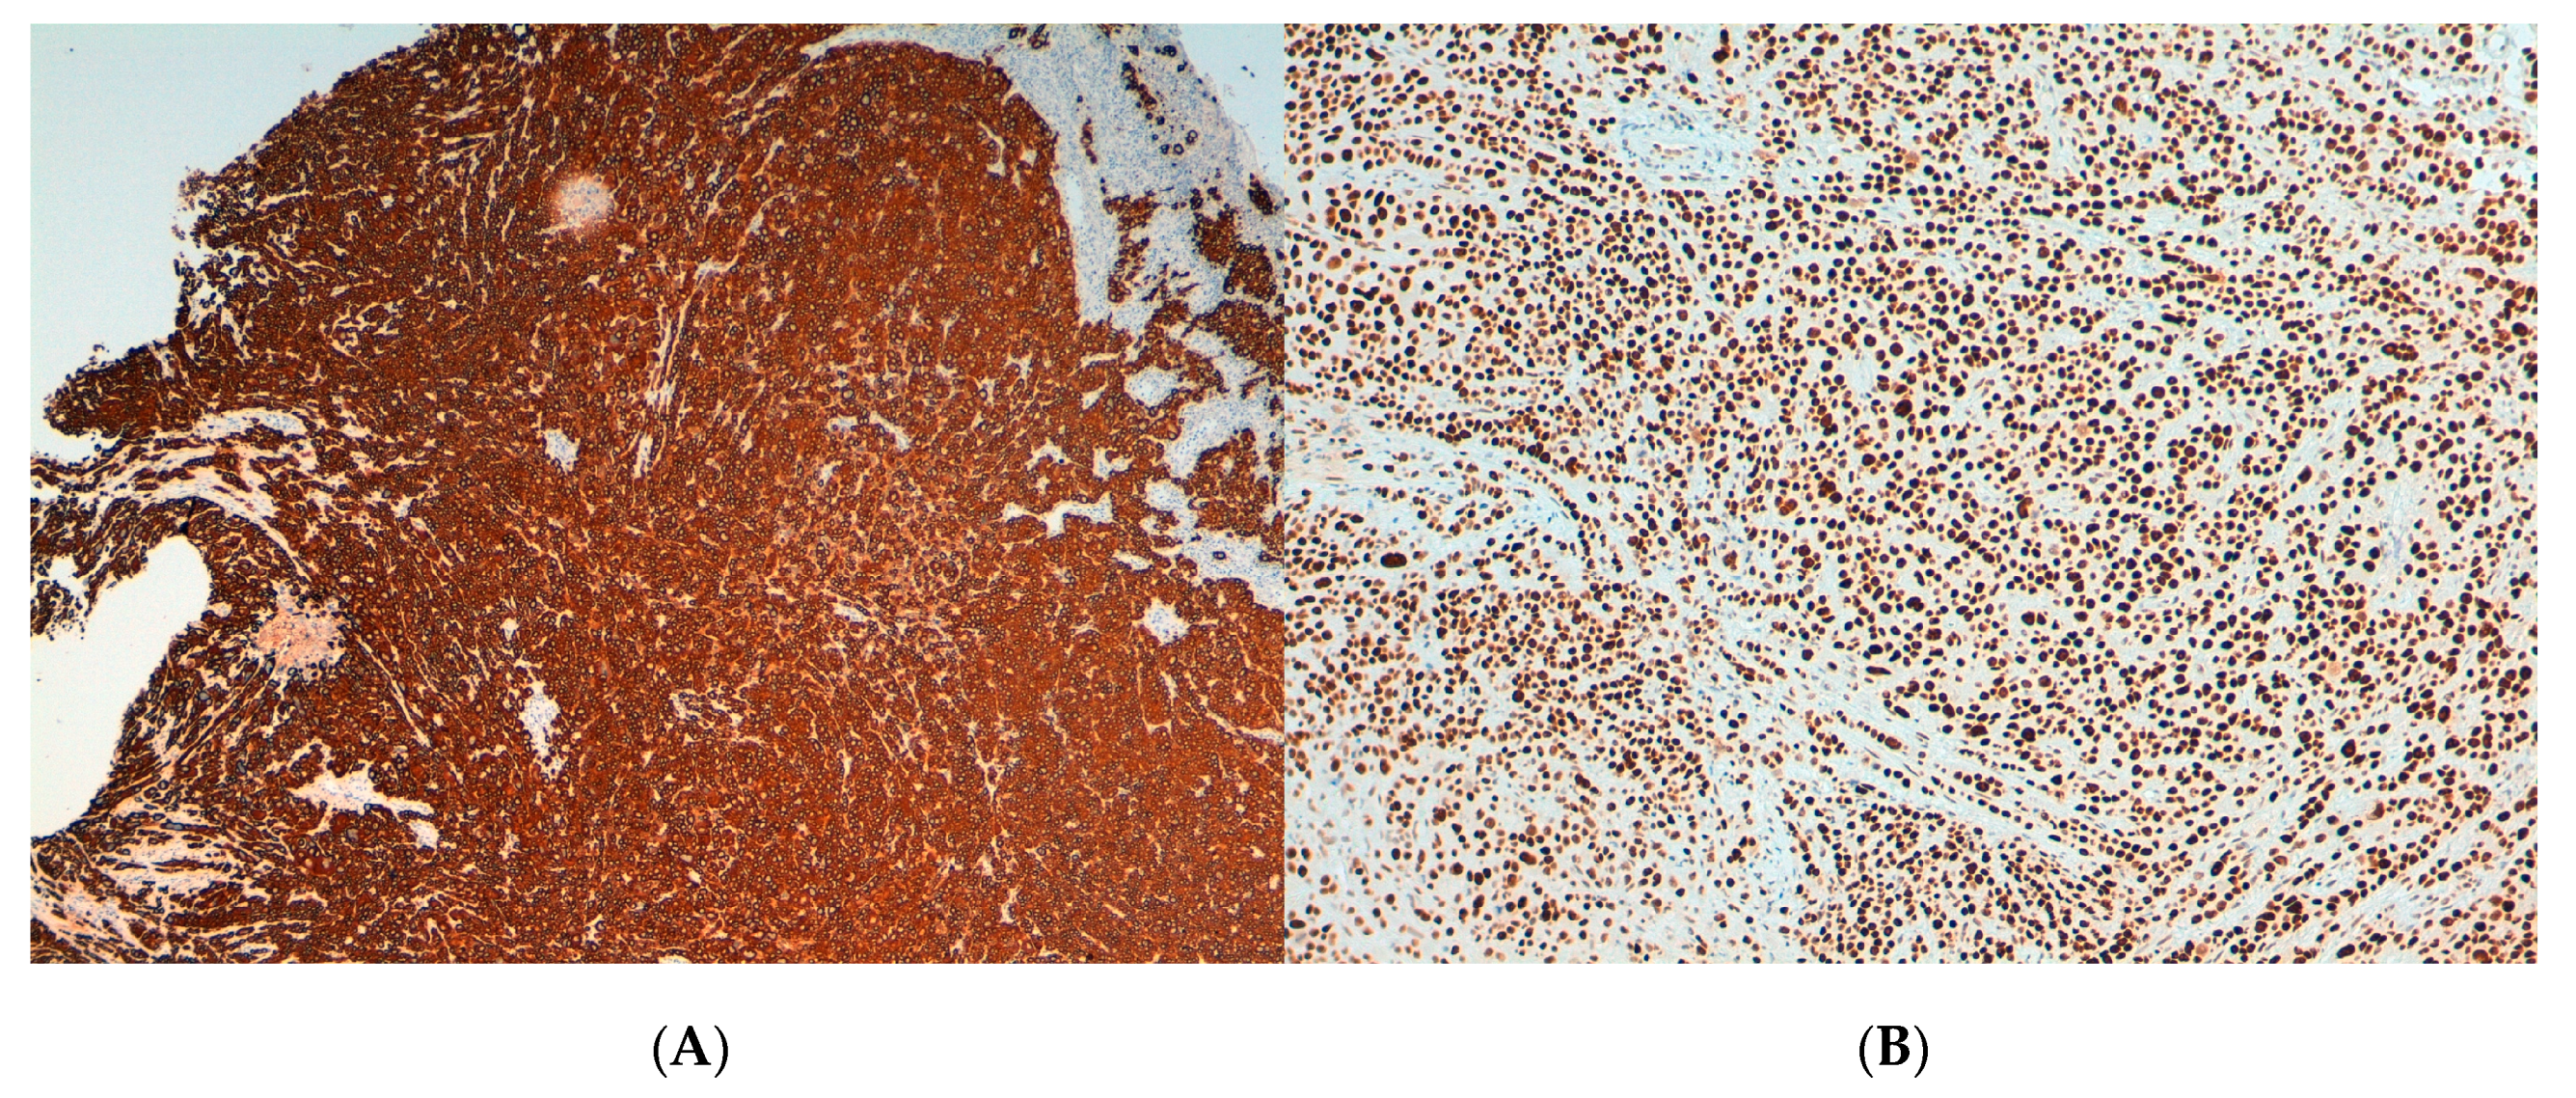

3.1. Pathological and Immunohistochemical Findings